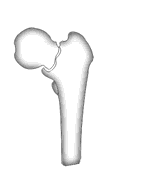

А что насчет остеостомии типа как на картинке в приложении?

Вчера сделали остеотомию, делали близко к тому, как на той картинке.

Картинка тут.

То, что получилось, в приложении (без такой красивой анимации, к сожалению